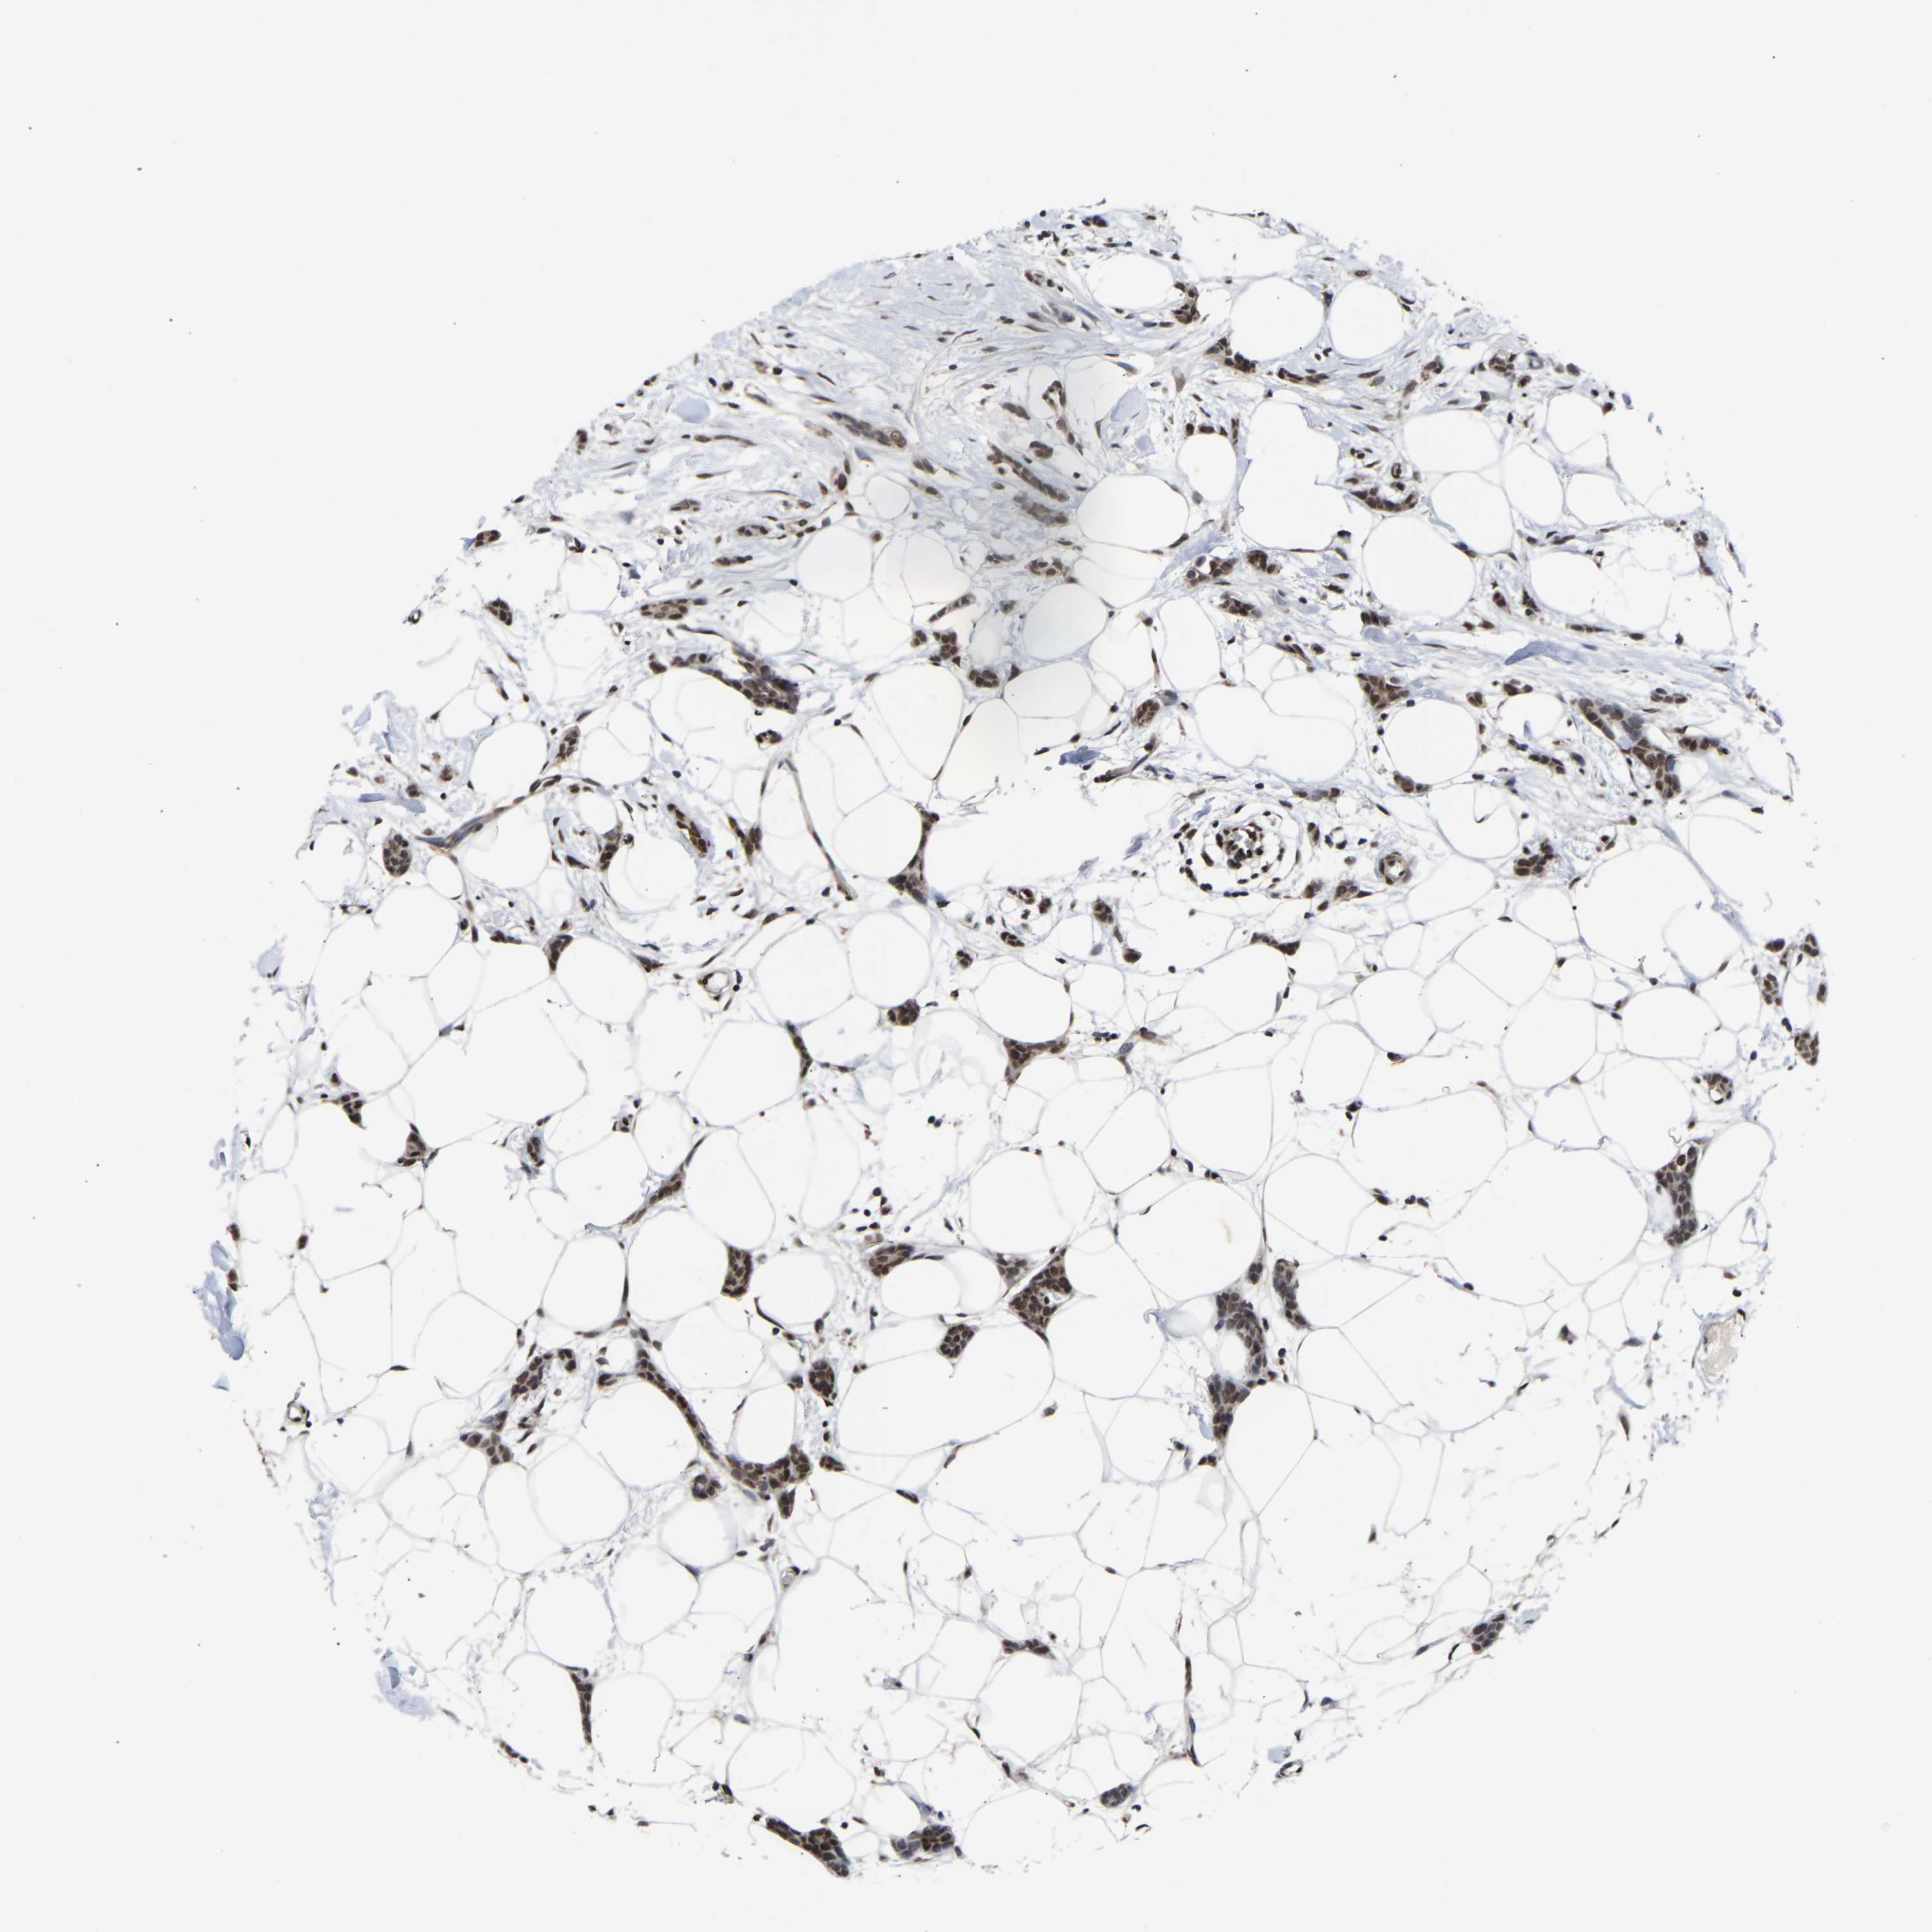

CANCER BREAST CANCER Show tissue menu

BRCA TCGA BRCA VALIDATION PROTEIN EXPRESSION